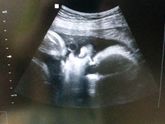

Сегодня 3 скрининг. Надеюсь наш малыш хоть в этот раз не будет вредничать и покажет кого мы ждем) Наш папа уже с самого утра начал отсчет часов до УЗИ. Очень жаль что его не будет рядом,командировка-будь она не ладна...